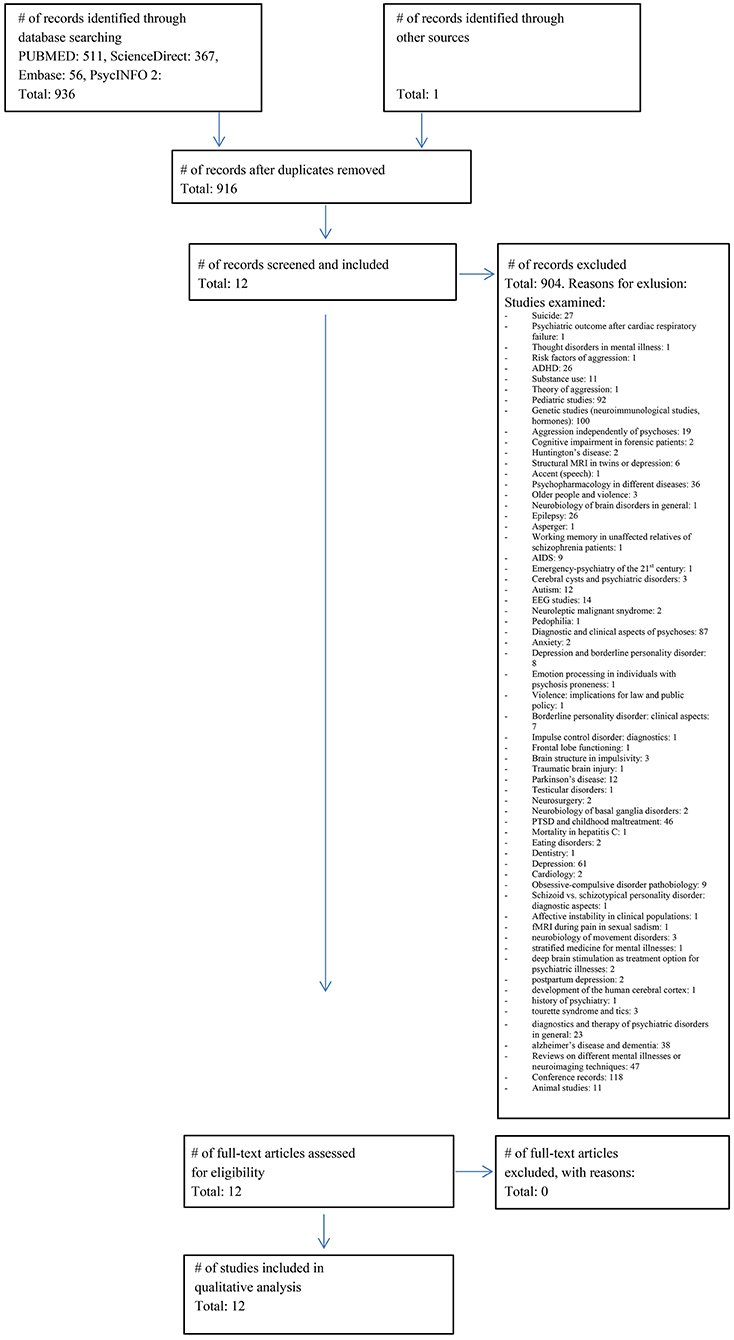

The literature search identified 937 studies of interest. After screening and applying in- and exclusion criteria, 925 studies were excluded. Main reasons for these numerous exclusions were that included persons did not fulfill the relevant diagnostic criteria or that the paper did not examine correlates of aggression. The exact number of studies with specific reasons for exclusion are detailed in Figure 1.

Figure 1. Prisma flow chart. Flowchart of the literature search (03.09.2017) and included studies according to the PRISMA guidelines (20).

Using the PRISMA template, we summarize the study selection procedure in Figure 1.

The final sample consisted of 12 studies with a total of 334 patients and 113 HC. After subtracting subject overlaps due to the publication of multiple papers using the same cohort, the sample consisted of 236 patients and 92 HC subjects. Barkataki et al. (26), Kumari et al. (27), and Kumari et al. (28) as well as both Wong et al. (29) and Wong et al. (30) used the same underlying patient population.